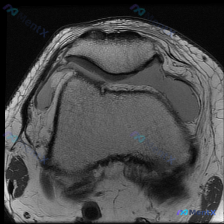

这是单张膝关节髌股关节水平的轴位T1加权MRI扫描图:

- 扫描层面:髌股关节水平,可见上方髌骨、下方股骨滑车沟的关节结构

- 骨骼:股骨远端骨皮质完整,骨髓信号均匀呈正常T1高信号;髌骨形态完整,骨髓无局灶性信号减低

- 关节软骨:髌骨后方关节面软骨、股骨滑车沟表面软骨厚度大致均匀,未见明确剥脱、局灶性缺损

- 软组织:髌骨内外侧支持带结构连续,无断裂或异常信号;周围皮下脂肪信号正常,无肿胀渗出

- 关节腔:关节间隙内无明显病理性低信号积液填充,髌股关节对位关系正常,无髌骨半脱位或侧向移位